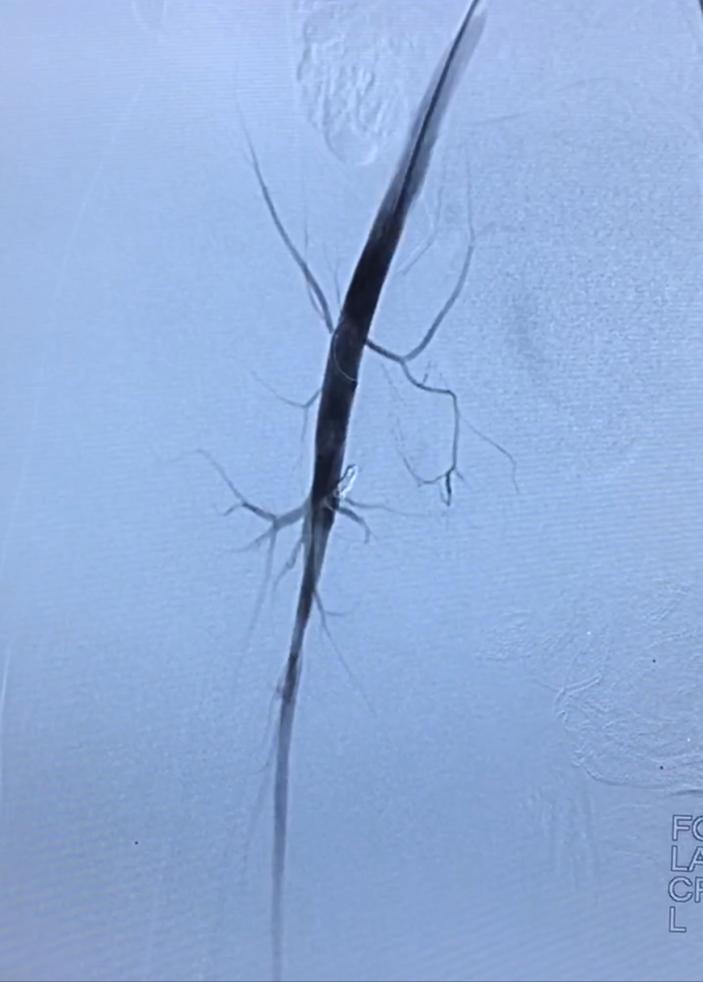

又试静脉端,照样难固定。经历了无数脱管,再超选,反复尝试,原本一个小时手术已经超过3个半小时,奇迹出现,多次尝试后终于让弹簧圈站稳了,位置恰恰好,瘘道完全栓塞。回病房后患儿卧床12小时,第二天就可以下床,出院。

介入术中造影可见瘘口,弹簧圈栓塞后消失

术后12月复查,患儿右下肢肿胀明显改善,表面的曲张静脉消失了。再次CT检查,瘘道消失,祝小姑娘早日康复!